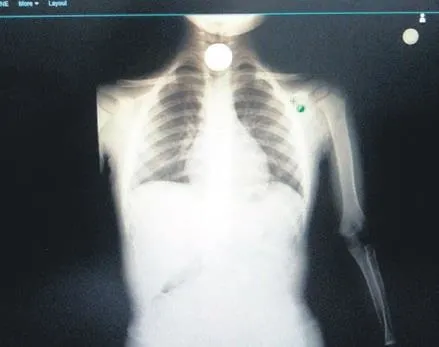

Afyonkarahisar'da 3.5 yaşındaki Miraç Özok, önceki gün rahatsızlandı. Öksürme, kızarma ve nefes alamama şikayetiyle hastaneye kaldırıldı. Yapılan incelemede, yemek borusunda 2 metal para olduğu anlaşıldı!

Hemen ameliyata alındı. Kritik bir operasyonla hayatta kaldı. Anne Ebru Özok, yaşadığı korku dolu anları şöyle anlattı: Ben mutfaktaydım. Yanıma gelerek para yuttuğunu söyledi. Önce inanamadım. Ancak sonra yüzü kızarmaya öksürmeye başladı. Su içirmeye çalıştım, içemedi. Hemen ambulansı aradık. Hastanede çekilen filmde para yemek borusunda görünüyordu. Vakit kaybetmeden yapılan tıbbı müdahaleyle sağlığına kavuştu çok şükür.